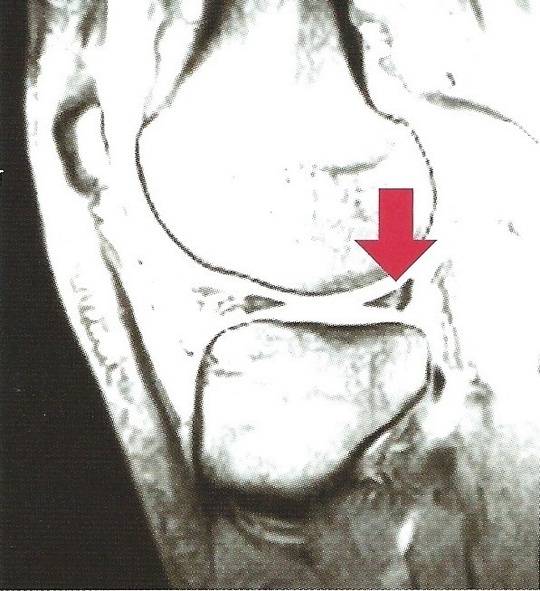

外側半月の水平断裂